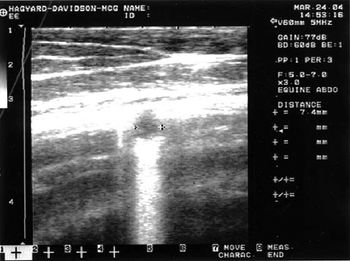

Shadow is a 7 yr, American Saddlebred Gelding.